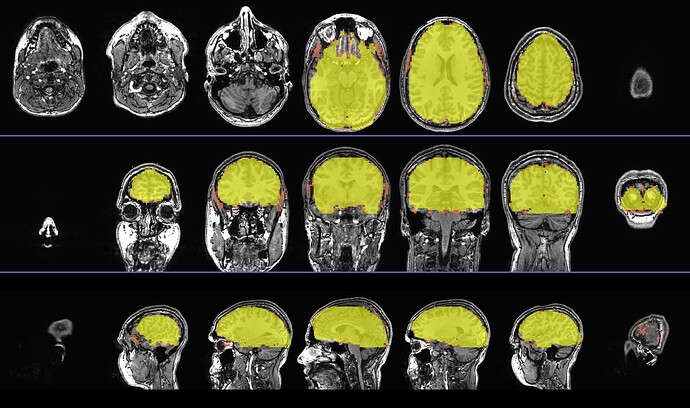

I got the sagittal and axial slice views, as well as the colorbar image with transparent thresholding noted, as follows:

AAA_qc_07_vstat_Full_Fstat.pbar

To set the colorbar ranges and thresholds is hard to generalize. What is your application of interest?